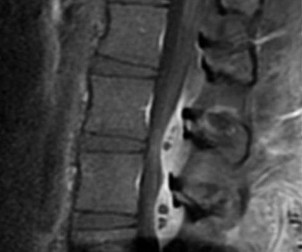

A 65-year-old male presents with classic symptoms of neurogenic claudication. He reports bilateral leg pain and fatigue that worsens with walking but is reliably relieved by leaning forward onto a shopping cart. In the pathogenesis of degenerative lumbar spinal stenosis, which structure is primarily responsible for dynamic central canal compression during spinal extension?

Explanation

In degenerative lumbar spinal stenosis, extension of the spine decreases the sagittal diameter of the canal because the ligamentum flavum buckles inward (shingling), dynamically compressing the thecal sac. Flexion of the spine pulls the ligamentum flavum taut, increasing the available canal space and alleviating neurogenic claudication symptoms. Hypertrophic ligamentum flavum is a major structural contributor to central stenosis.